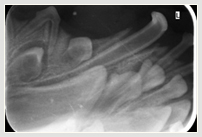

Zahnröntgen Unterkiefer - nicht ausgefallener Milchzahn Milchzähne im Unterkiefer nicht ausgefallen Milchzähne im Unterkiefer entfernt